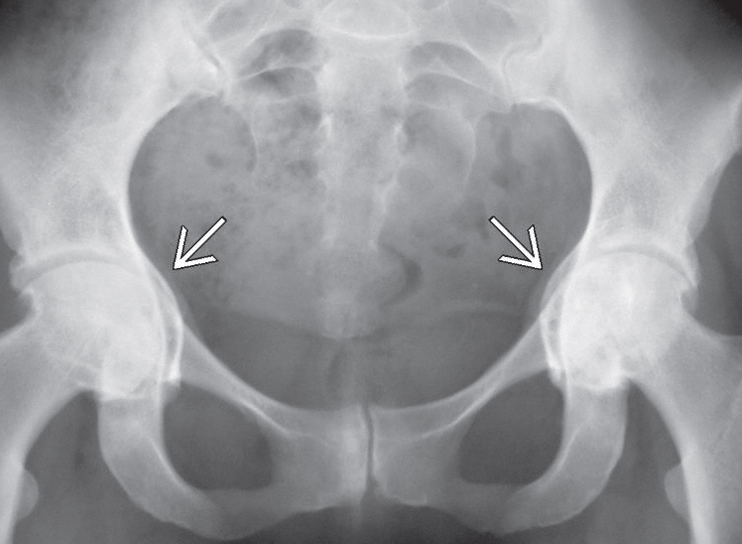

![]() |

| Normal ve artrit gelişmiş hastalara ait kalça filmleri | |